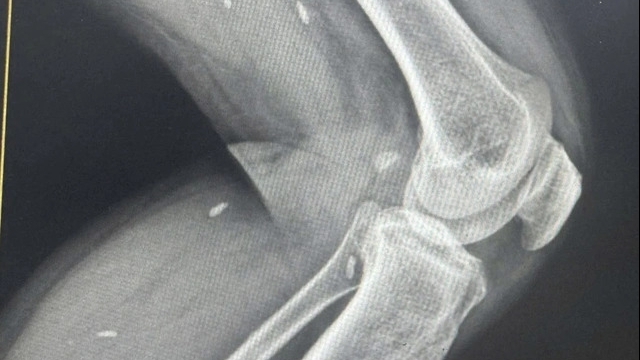

Con trai "bệnh nhân 175" đến khoa Chấn thương Chỉnh hình, Bệnh viện Xanh Pôn, khám hôm 19/3 do đứt dây chằng chéo gối trước trái. Ngày 25/3, người con này vào Xanh Pôn để phẫu thuật, nằm điều trị tại phòng X3, khoa Chấn thương chỉnh hình.